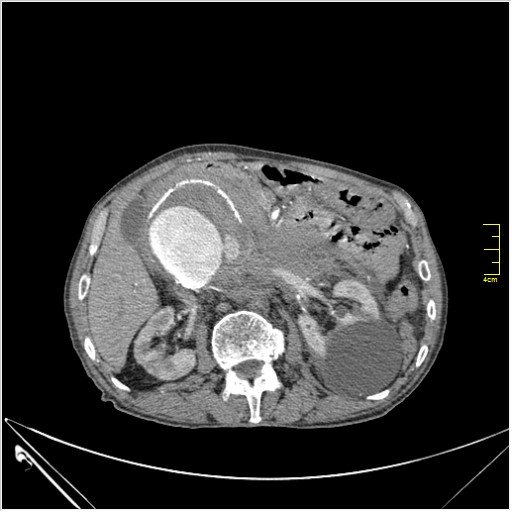

Пациент Т. 64 года, обратился на КТ брюшной полости амбулаторно (!), по направлению семейного врача с диагнозом abdominal mass, буквально: образование брюшной полости.

Huge abdominal aorta aneurism. Simple renal cortical cysts (Bosniak type 1).